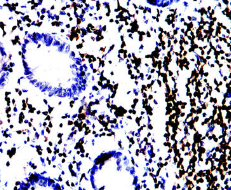

CD79A Mouse Monoclonal antibody[2E6A7]

AC1815 CD79A Mouse Monoclonal antibody[2E6A7] 100ug $367 10days

AC1815 CD79A Mouse Monoclonal antibody[2E6A7] 200ug $660.6 10days

Immunogen:    Purified recombinant fragment of human CD79A (AA: extra 33-143) expressed in E. Coli.

IHC    1/200 - 1/1000